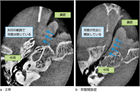

1. 図「耳管機能検査装置TTAG法による鼓膜の呼吸性動揺の診断」および「軟口蓋が上がらない音声⇒聴診による開放耳管の診断」をアップデートした。

診断

1. 鼻すすり型耳管開放症と非鼻すすり型耳管開放症を区別して診断する。